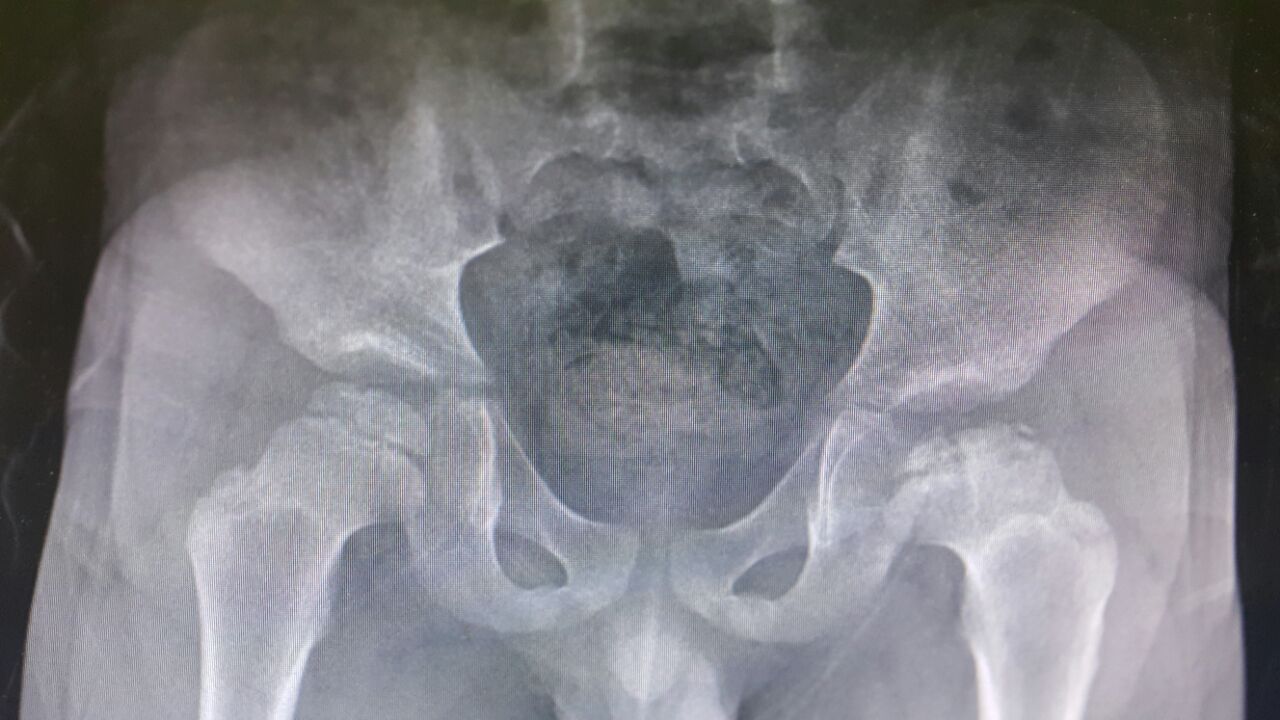

Kalça çıkığı, eklemi oluşturan uyluk kemiğinin başı ile kalça yuvası arasındaki normal ilişkinin bozulması ve eklemin normal gelişememesi şeklinde kendini gösteren bir kas iskelet sistemi hastalığıdır. Kalçalar genellikle doğumu izleyen haftalar içinde çıkmakta, bebeğin büyümesi ile kalça gelişimi geri kalmakta ve zamanla kötüleşmektedir.

Kalça ekleminde çıkık olmadan görülebilen eklem gelişim bozukluğu da önemli bir problemdir. Kalça gelişimi geri kalmakta, çıkığa meyil görülmekte, genç yaşta ağrı ve kireçlenmelere neden olabilmektedir.

Her bebek kalça çıkığı açısından doğumu izleyen en kısa sürede bir ilgili çocuk hastalıkları veya ortopedi uzmanı tarafından muayene edilmelidir. Sadece klinik muayene ile çıkık kalçaların önemli bir kısmı gözden kaçabilmektedir. Tanı amacıyla çekilen röntgen filmlerinden genellikle ilk 6 ayda kısmi bilgi alınabilmekte, bu nedenle kesin tanıya ulaşılamamaktadır.

Erken dönemde basit yöntemlerle düzeltilip normal kalça elde edilebilirken geç kalınanlarda normal kalça elde edilememekte ve hastaya ancak yardımcı olunabilmektedir. Eğer kalça yerine oturuyorsa tedavi için ilk 6 ay içinde bandajlama veya ortez kullanımı, 6. ila 18. ay arasında alçılama genellikle yeterli olmaktadır. Eğer çıkık kalça yerine kolaylıkla ve tam oturmuyorsa tedavi için ameliyat kaçınılmazdır. Ne kadar erken yakalanırsa o kadar iyi sonuç alınmakta, gecikmesi halinde birden fazla ameliyat gerekmekte ve hatta ileri erişkin yaşlarda kalça artroplastisi denen eklem değiştirme ameliyatlarına ihtiyaç duyulmaktadır. Kalça çıkığı tanısı konanlarda hastanın ömür boyu düzenli takibi gereklidir. Bu hastalara uygulanan tedavilerin kayıtları, çekilen röntgen grafileri, hastalara verilen taburcu notları ömür boyu saklanmalı, bu belgeler hastaneye kalça yakınması ile her gelişte mutlaka yanında bulundurulmalıdır.